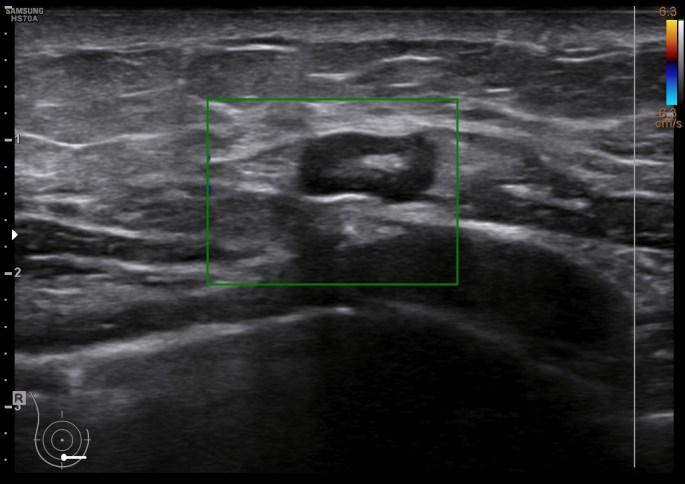

En las mastitis, al ser procesos infecciosos, no es raro ver gánglios intramamarios aumentados de tamaño o reactivos que hayan perdido su centro graso. En este caso, en localización muy próxima. Observa el aspecto habitual en forma de judia con centro hiperecogénico graso y corteza hipoecogénica, imagen 4.